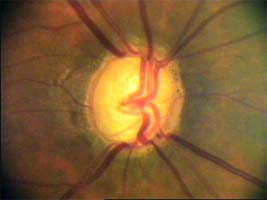

Cévy

Jaké informace nám mohou říci cévy o poškození terče glaukomem? Cévy kopírují povrch terče, jeho nerovnosti se projevují záhyby cév. Při glaukomu mohou být obnaženy cévy, které dříve probíhaly v n. lemu. Při pokročilého glaukomu se zužují arterie a vzniká arteriovenózní nepoměr!

Na dolním pólu terče je patrný zálom vény, která zviditelňuje přítomnost i hloubku exkavace až k dolnímu okraji terče.

V nasálním horním kvadrantu terče vidíme obnažené cévy, které dříve probíhaly v lemu. Toto obnažení může být jedním z prvních příznaků glaukomové neuropathie.